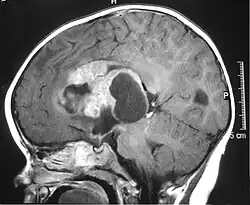

Tumeur tératoïde rhabdoïde atypique

La tumeur tératoïde rhabdoïde atypique (abrégé ATRT, selon l'anglais atypical teratoid rhabdoid tumor) est un type de tumeur rare, surtout diagnostiquée chez les enfants[1]. Elle se situe le plus souvent dans le cerveau, mais peut se trouver à n'importe quel autre endroit dans le système nerveux central, moelle épinière incluse[réf. souhaitée].